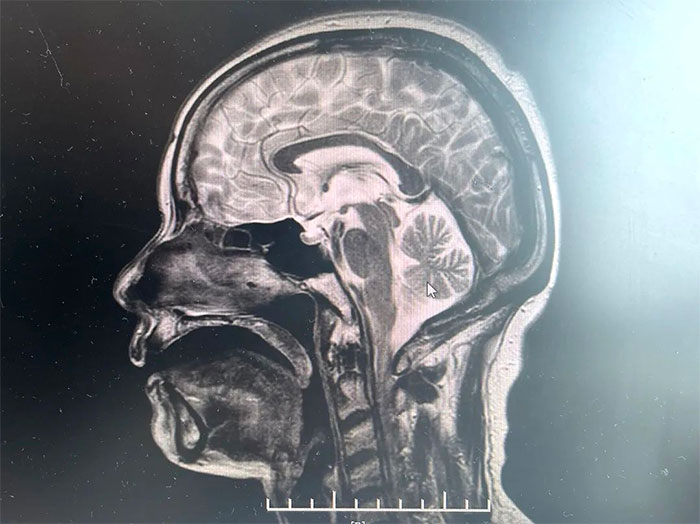

▲ MRI影像提示符合多系統(tǒng)萎縮表現(xiàn)

經(jīng)磁共振(MRI)檢查顯示,林女士橋腦“十字征”、“殼核裂隙征”、“小腦萎縮”,符合多系統(tǒng)萎縮影像表現(xiàn),再次驗證了李振并主任的臨床判斷——多系統(tǒng)萎縮。